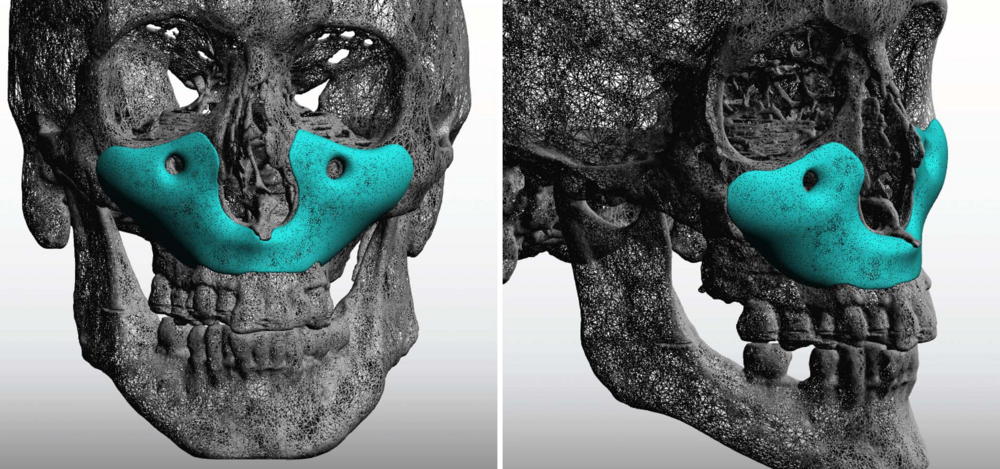

3. CUSTOM FULL MIDFACE IMPLANT https://exploreplasticsurgery.com/the-aesthetic-impact-of-a-custom-total-midface-implant/

3. CUSTOM FULL MIDFACE IMPLANT https://exploreplasticsurgery.com/the-aesthetic-impact-of-a-custom-total-midface-implant/